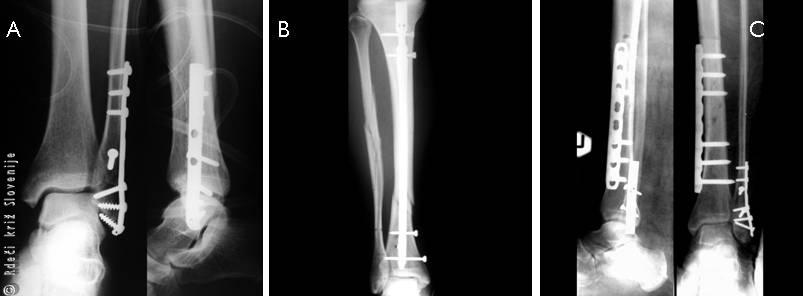

Slika 20

A – Zlom gležnja, oskrba s ploščo in vijaki.

B – Zlom goleni, oskrba z intramedularnim žebljem, fiksacija kosti z žebljem v kostnem mozgu.

C – Zlom goleni, oskrba zloma golenice z LCP ploščo, ki deluje kot notranji fiksator.